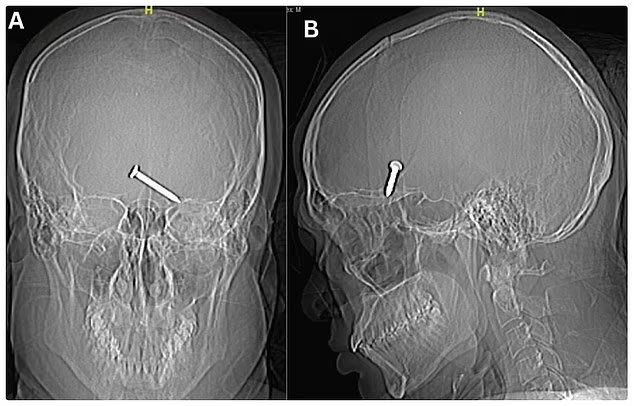

Малайзийские хирурги удалили трёхсантиметровый гвоздь из головы пациента и он в целом остался жив. О необычном случае рассказывает Daily Mail в пятницу.

Гвоздь вошёл в его голову через левый глаз в нескольких миллиметрах от зрачка. Пострадавшего экстренно госпитализировали в больницу Султанах Бахия в Алор-Сетаре на западном побережье Малайзии.

Удивительно, но инородное тело, попав в жизненно важные для движения и речи лобные доли, не нанесло критических увечий. Врачи сумели его удалить вместе с повреждёнными тканями.

Гвоздь в голове — рентгеновский снимок